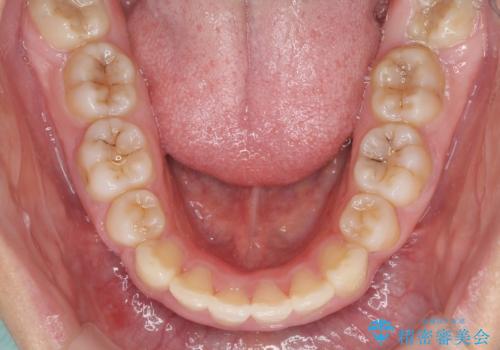

しっかりと通院するようになってからは順調に治療が進み、横顔の印象が変わるほどスッキリとした口元となりました。

口元を積極的に引っ込めるために、上下左右の第一小臼歯を4本抜歯することとしました。